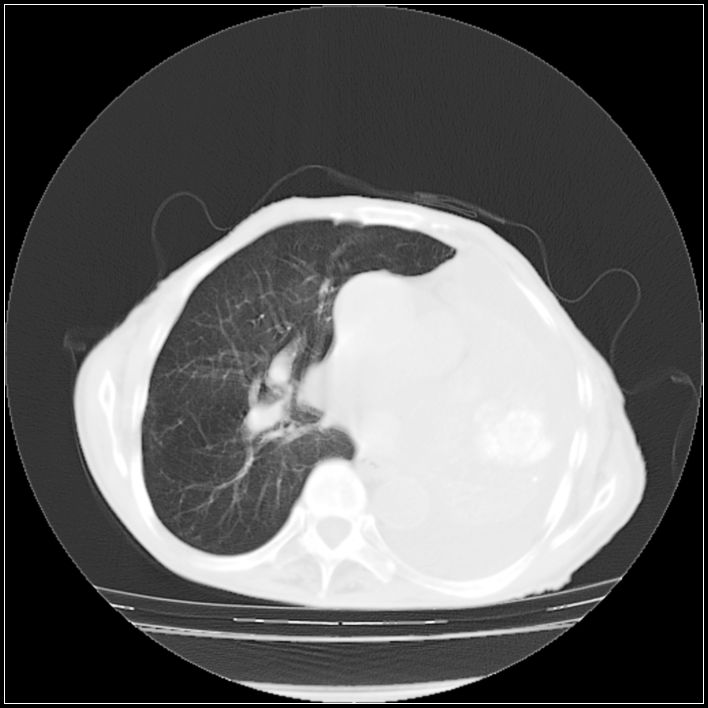

以下是引用ydx_74在2008-5-31 16:08:00的发言:[br]中心性肺癌并左侧肺不张、胸水。

以下是引用影象小辈在2008-5-31 16:25:00的发言:[br]左侧胸腔团状不规则致密影,界欠规整,密度不均匀,其内可见更低密度影及高密度影,并可见包裹性胸腔积液 考虑为1.畸胎瘤 2.肺癌